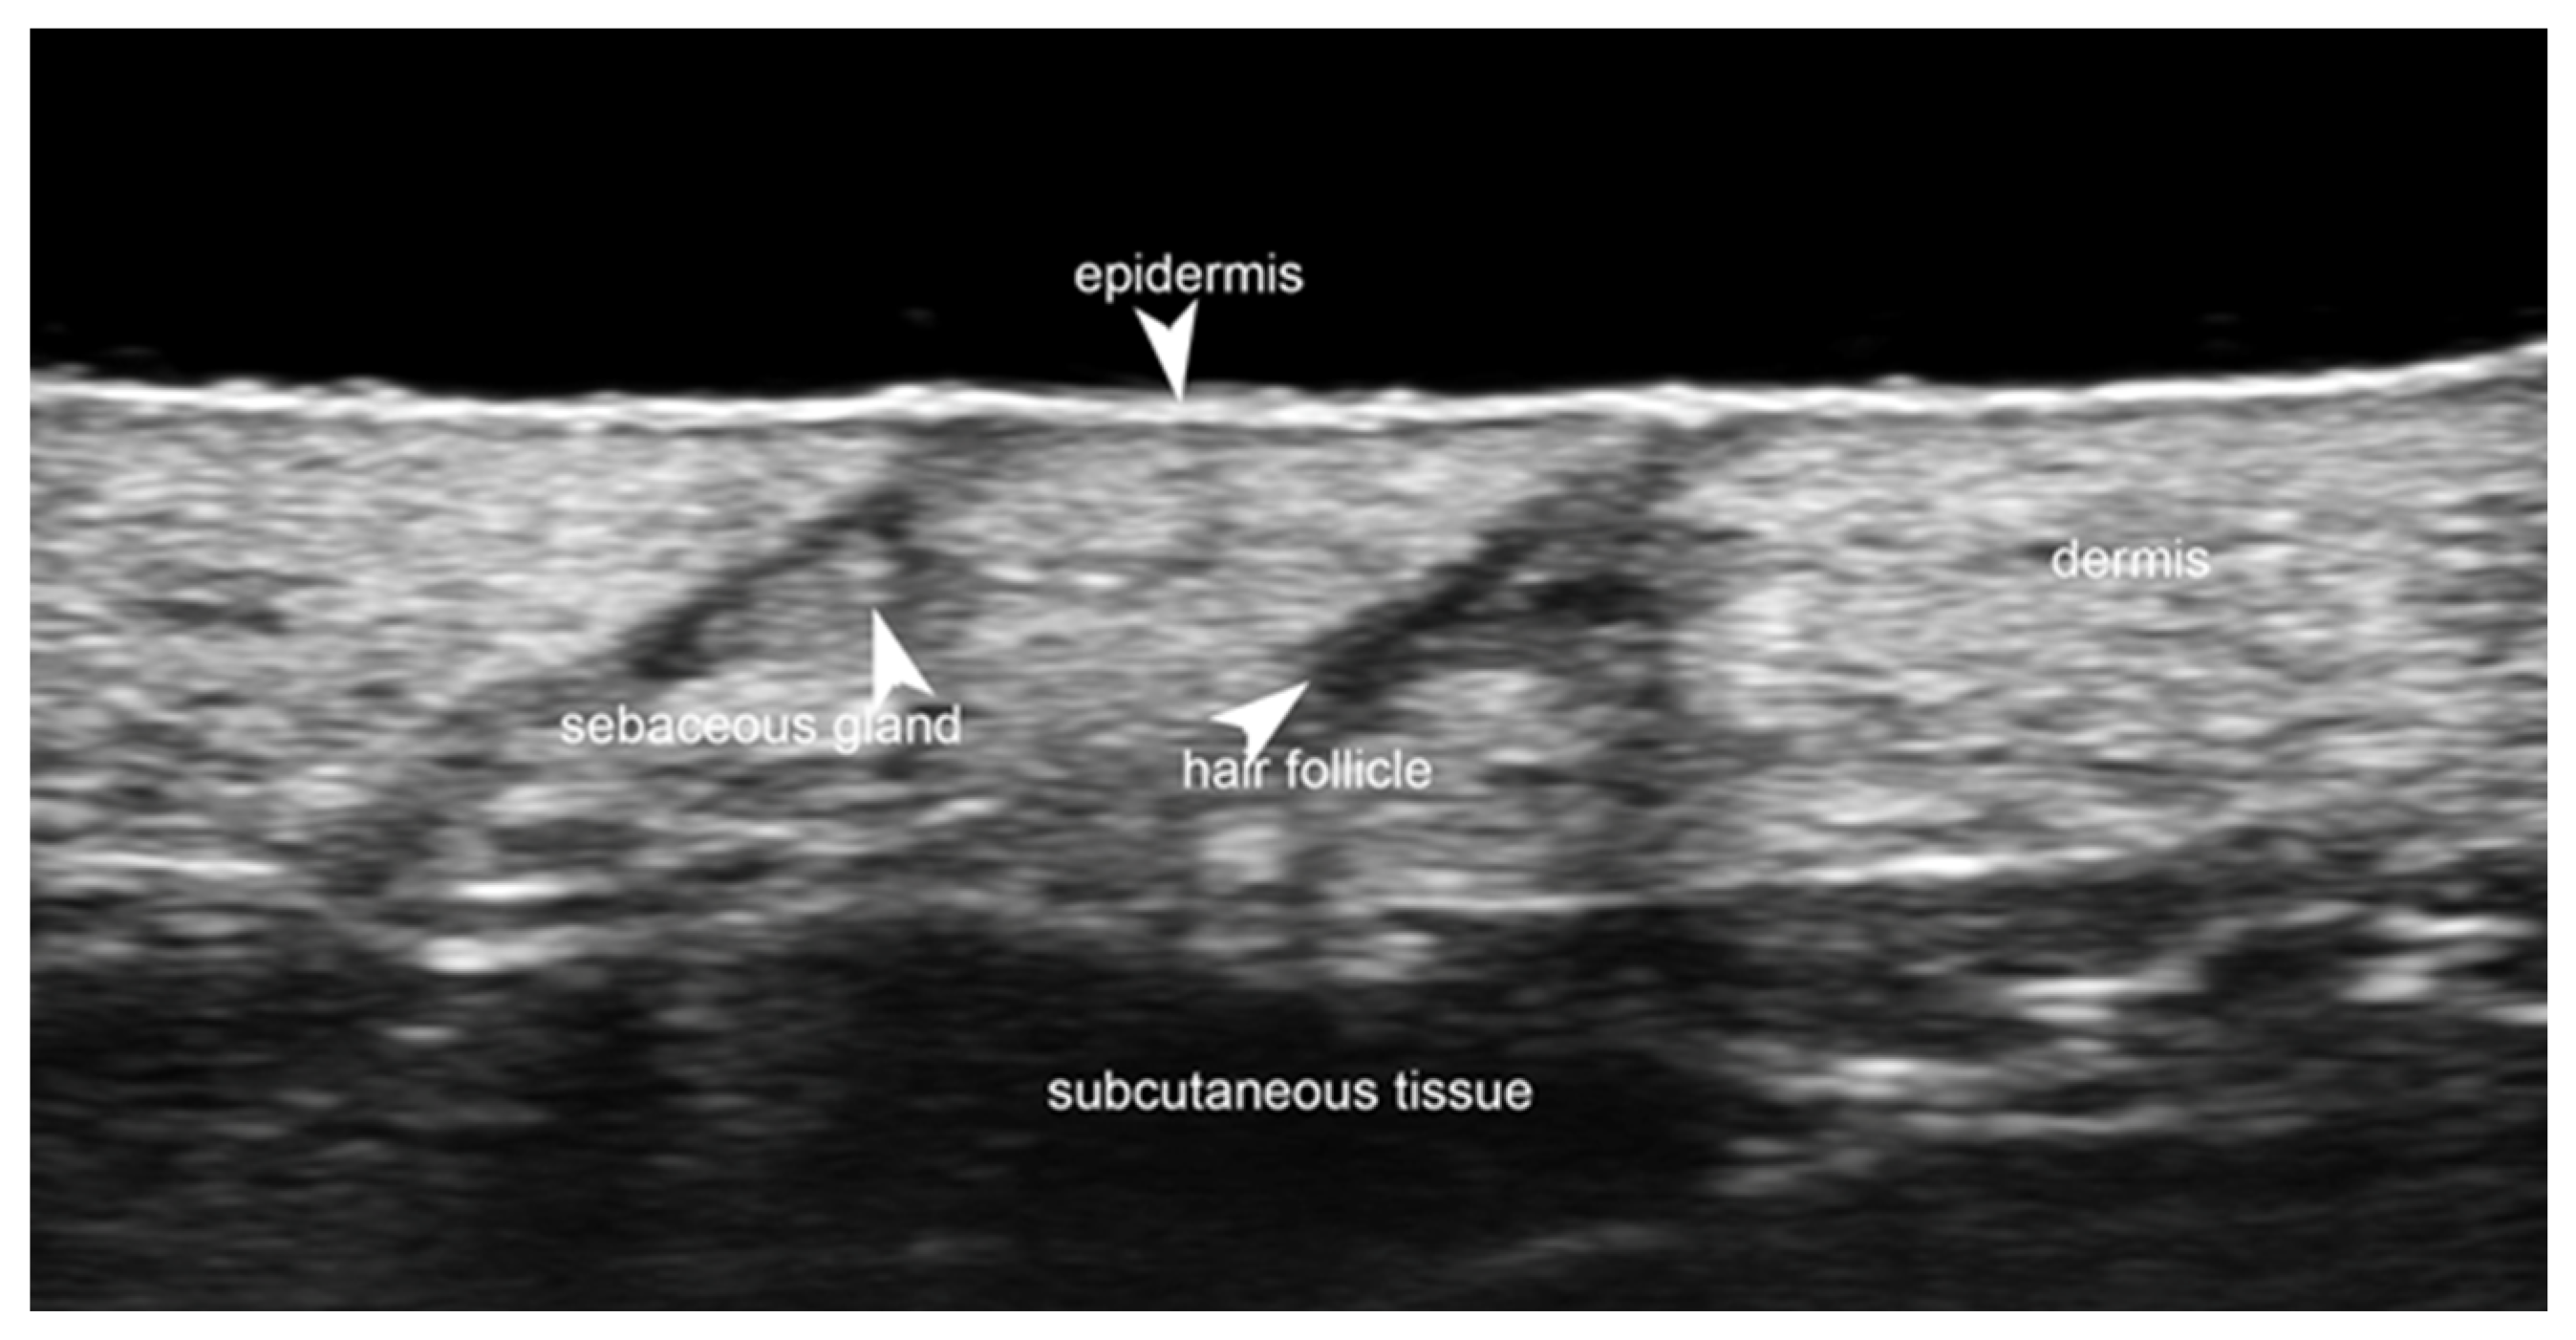

- Gonzalez, C.; Wortsman, X. How to Start on Dermatologic Ultrasound: Basic Anatomical Concepts, Guidelines, Technical Considerations, and Best Tips. Semin. Ultrasound CT MRI 2024, 45, 180–191. [Google Scholar] [CrossRef] [PubMed]